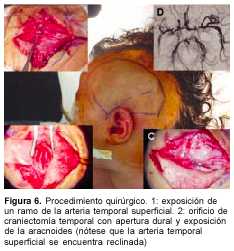

Más recientemente se ha comenzado a utilizar una técnica de revascularización indirecta llamada pialsinangiosis. Fue descripta por Adelson y Scott(25,26). Se postula que el contacto directo de la arteria temporal superficial con la superficie cerebral potencia aún más la formación de vasos colaterales nuevos y no se considera necesaria la apertura de aracnoides ni la sutura de ésta a la arteria, como en la EDAS. Esta novedosa técnica hace más sencilla y menos riesgosa la cirugía.

A los 3 meses de edad consultó por hemiplejia izquierda y retraso psicomotor. La tomografía computada (TC) de cráneo demostró un infarto hemisférico derecho (figura 1). Los estudios complementarios pusieron de manifiesto una coartación de aorta torácica descendente, sin evidencia de patología arterial sistémica. A nivel encefálico se estudió con angiografía de cuatro vasos de cuello, que demostró la existencia de una enfermedad de moyamoya (figuras 2 a 4). En ese momento no se consideró el tratamiento quirúrgico y una vez estabilizada se otorgó el alta. La coartación de la aorta no requirió cirugía y no se investigó el eventual nexo con la enfermedad de moyamoya. A los 8 meses de edad comenzó con hemiparesia derecha progresiva, lo que junto a su hemiplejia izquierda agravó su déficit motor severamente. Ingresó al Centro Hospitalario Pereira Rossell a los 10 meses. El examen del ingreso mostraba retardo neuropsíquico, hemiplejia izquierda espástica y hemiparesia derecha severa, que apenas vencía gravedad y no oponía resistencia. Una nueva TC mostró como elemento agregado al infarto derecho previo, una isquemia hemisférica izquierda (figura 5). Se resolvió realizar una revascularización quirúrgica del hemisferio izquierdo. Se intervino (figura 6) en el Servicio de Neurocirugía Pediátrica del Hospital. El procedimiento realizado fue una pialsinangiosis, con disección de la arteria temporal superficial izquierda con galea satélite y la sutura del tejido periarterial a la aracnoides temporal. La evolución posoperatoria fue buena, con recuperación progresiva de la función motora del hemicuerpo derecho. En forma gradual también comenzó a recuperar motricidad de su hemicuerpo izquierdo, anteriormente pléjico, y a mejorar sus performances, comenzando a pronunciar palabras a los cuatro meses, aunque manteniendo un retraso en el desarrollo psicomotor. Al año de operada se constató leve hemiparesia izquierda, ausencia de elementos deficitarios motores a derecha y persistencia de alteraciones en el lenguaje. Una ARM realizada a los diez meses de la operación mostró desarrollo de circulación colateral hacia el área quirúrgica (figura 7). Una TC de control permitió ver el infarto secuelar de hemisferio derecho y disminución franca de la hipodensidad del hemisferio izquierdo a los 18 meses de operada (figuras 8 y 9).

En una segunda etapa, ya con 10 meses de edad, ante la agravación progresiva del déficit motor, que avanzaba hacia una tetraplejia, se impuso la necesidad de tratamiento quirúrgico. La técnica quirúrgica elegida fue la pialsinangiosis por considerársela la más efectiva, con la ventaja de ser segura y relativamente sencilla. Según un estudio de Choux y colaboradores(27), midiendo la cantidad de vasos colaterales nacidos a partir de la arteria cerebral media y comparando los resultados de la pialsinangiosis y la EDAS, se encontraron 85% de resultados buenos o excelentes con la pialsinangiosis y 15% de resultados similares con la EDAS. Esta diferencia radicaría en la importancia que tiene el factor de crecimiento fibroblástico básico (bFCF), que, como se ha mencionado, es uno de los más potentes factores angiogénicos de la economía y está notablemente incrementado en esta enfermedad(9). Al abrir la capa aracnoidal se expondría la superficie arterial (vaso donante) a este potente factor, lo que redundaría en mayor cantidad de colaterales y en forma más precoz. Las mediciones de bFCF en el LCR podrían servir como predictor de cuál paciente respondería mejor a esta técnica.